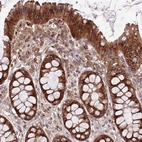

Immunohistochemical staining of human liver shows strong cytoplasmic/cytoplasmic granular positivity in hepatocytes.